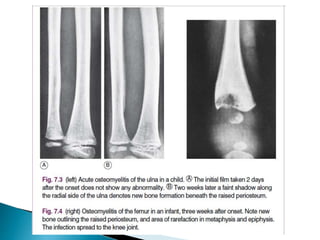

• 1st 10 days Show No Abnormality .

Only after two or three weeks do visible changes appear, and they

may never do so if efficient treatment is started very early.

• By the end of the 2nd Week signs of rarefaction of

Metaphysis and New Bone Formation. Then sigs of

healing

• Soft-tissue edema at 1-3 days after start of infection.

• Bony changes are not evident for 14-21 days:

– Early radiographic signs of rarefraction (thining of

bony tissue sufficient to cause decreased density of

bone) of the metaphysis and new bone formation

outlining the raised periosteum

– Sclerosis and thickening of the bone cortex at

• Approximately 40-50% focal bone loss is necessary to

cause detectable lucency on plain films; a negative X-

Ray does not exclude osteomyelitis